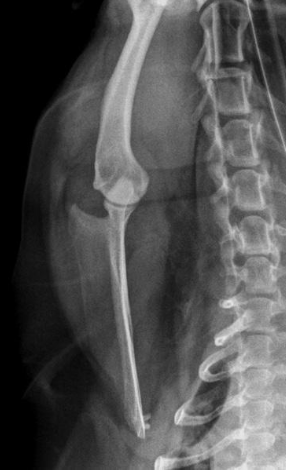

what radiographic view of the humerus is shown?

lateral view